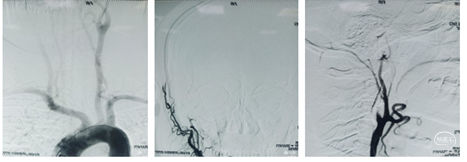

脑血管造影:左侧颈内动脉C 1段呈火苗样,考虑T型段闭塞可能。右侧颈内动脉通过前交通向左侧大脑中动脉区域代偿供血。后交通向左侧大脑中动脉区域供血。可能考虑FLER已经出现病灶,未进行急性血管开通。

导引导管到位:右侧股动脉置8F动脉鞘,0.035泥鳅导丝携带单弯导管外衬8F导引导管到达右侧颈总动脉近分叉处。撤出单弯导管和泥鳅导丝。

裸奔抽吸:通过导引导管将中间导管0.070-125cm置于颈内动脉起始部,"裸奔"边抽吸边上,抽吸3次,到达C4段,但以远血管仍不通畅。

导丝导引下抽吸:微导丝携带微导管,在中间导管支撑下到达C6-M1起始部,中间导管再次边抽吸边上至M1起始部,抽出部分血栓,中间导管造影示大脑前通畅,大脑中动脉仍不通。